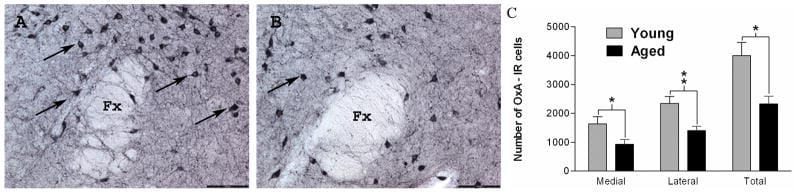

Earlier work by Kessler et al. (2011) established that orexin neuron attrition is a normal part of aging, not exclusively a disease process. Their rodent data showed more than 40% orexin neuron loss in aged rats, while human research has shown a similar trajectory at a lower magnitude. This was an important distinction: before this work, orexin neuron loss was primarily associated with narcolepsy, a condition involving 85-95% destruction of the orexin neuron population.

2. Kessler, B. A., Stanley, E. M., Frederick-Duus, D., & Fadel, J. (2011). Age-related loss of orexin/hypocretin neurons. Neuroscience, 178, 82-88. PMID: 21262323. https://pubmed.ncbi.nlm.nih.gov/21262323/